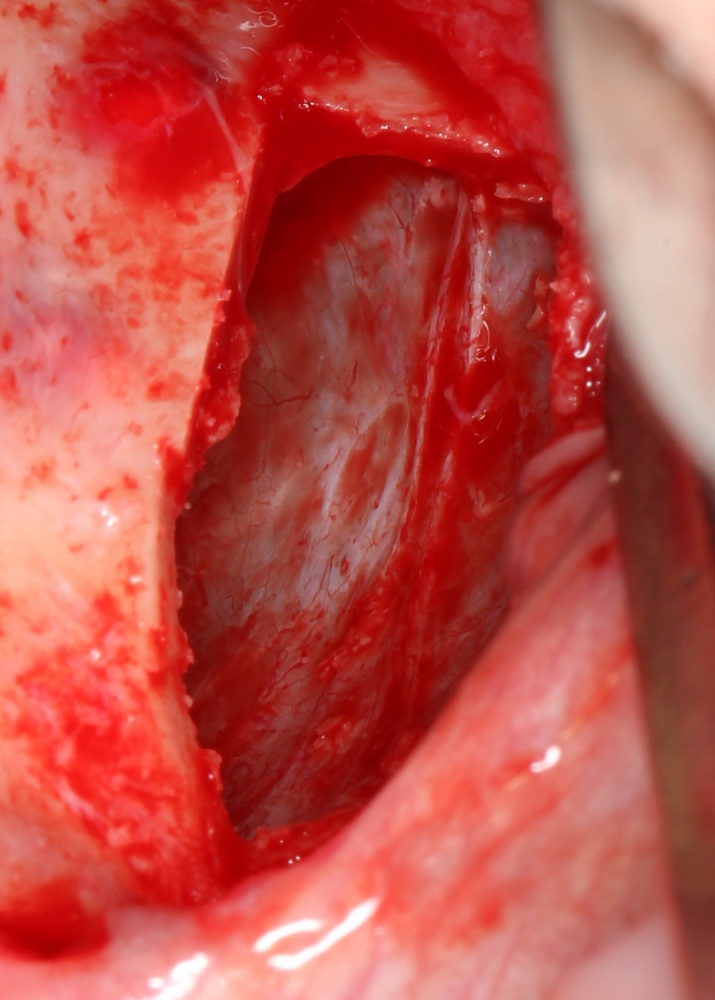

Создание субантрального пространства

Это, пожалуй, самый ответственный и деликатный этап хирургической операции. Слизистая оболочка отслаивается от внутренних стенок антрума (гайморовой пазухи) с помощью специальных инструментов, поднимается на необходимую высоту (рис 35).

Рисунок 35. Создание субантрального пространства.